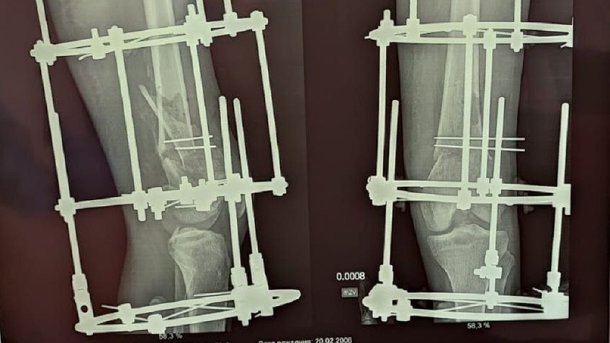

Фото: Пресс-служба Минздрава Омской области

Девочке диагностировали сложный оскольчатый перелом. Ей экстренно провели сразу две операции.

«Шейка бедра была сломана — а это то, за счёт чего мы вообще опору даём и благодаря чему есть движение в тазобедренном суставе. Плюс оскольчатый перелом был в дистальном отделе, где коленный сустав. Было большое количество отломков, нужно было всё застабилизировать. Был риск несращения, так как идёт размозжение тканей вокруг», — рассказал Максим Перфилов, врач травматолог-ортопед.

Операция длилась более трёх часов, ногу практически собирали по частям. Долгое время девочка проходила реабилитацию, посещала контрольные осмотры и соблюдала все рекомендации врачей. Аппарат Илизарова, который ей поставили, был снят — теперь юная омичка ходит сама, не испытывая боли.